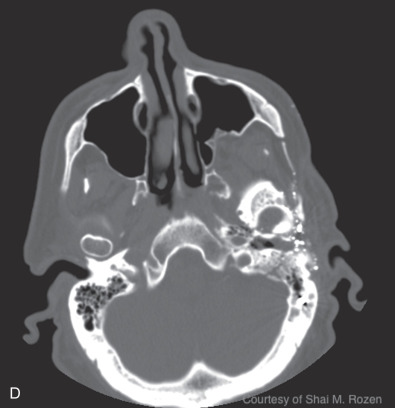

Temporal bone fractures are a product of high-energy blunt trauma commonly resulting in fracture, hemorrhage, nerve trauma, vascular damage, with disruption of the middle or inner ear structures, classically classified into longitudinal, transverse, or oblique fractures. Longitudinal fractures often result from lateral to medial forces extending through the facial nerve canal, possibly causing intraneural hemorrhage, transection, or bone compression. They can disrupt the ossicular chain, resulting in conductive hearing loss. Transverse fractures often result from anterior posterior forces with a fracture line often traversing the vestibulocochlear apparatus causing sensorineural hearing loss and equilibrium disorders. Transverse fractures more commonly injure the facial nerve due to proximity to the nerve’s labyrinthine segment. Oblique, also termed mixed, fractures include both longitudinal and transverse components. Additional classifications are based on degree of involvement of the petrous portion of the temporal bone, or the otic capsule. Temporal bone computed tomography (CT) scans should be performed in thin-section 1 mm cuts to avoid interpreting normal suture lines as fractures.

Blunt injuries resulting in temporal bone fractures are often encountered in motor vehicle accidents, altercations, or falls from heights. Approximately 7%–10% of temporal bone fractures result in facial nerve injury. Temporal bone fractures have several classifications. Fracture line orientation relative to the petrous bone defines fractures as longitudinal (70%–80%), transverse (10%–20%), and oblique (10%). Facial paralysis occurs most commonly in transverse fractures (50%) but may also occur in longitudinal fractures (25%). More modern CT-based classifications assess whether fractures are otic capsule sparing or violating, the latter being twice as likely to cause facial paralysis. Four types of facial nerve trauma have been found in temporal bone fractures. In 76% of longitudinal fractures either bony impingement or intraneural hematoma was found, and in 15% the nerve was transected. In the remainder of patients, no visible pathology was found other than neural edema. In transverse fractures, 92% were transected and 8% had impingement ( Fig. 1.5.3 ). Similar to penetrating intracranial facial nerve injuries, surviving patients are initially often in critical condition and the facial paralysis is often unnoticed.